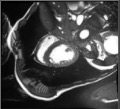

Despite their outstanding accuracy, semi-supervised segmentation methods based on deep neural networks can still yield predictions that are considered anatomically impossible by clinicians, for instance, containing holes or disconnected regions. To solve this problem, we present a Context-aware Virtual Adversarial Training (CaVAT) method for generating anatomically plausible segmentation. Unlike approaches focusing solely on accuracy, our method also considers complex topological constraints like connectivity which cannot be easily modeled in a differentiable loss function. We use adversarial training to generate examples violating the constraints, so the network can learn to avoid making such incorrect predictions on new examples, and employ the Reinforce algorithm to handle non-differentiable segmentation constraints. The proposed method offers a generic and efficient way to add any constraint on top of any segmentation network. Experiments on two clinically-relevant datasets show our method to produce segmentations that are both accurate and anatomically-plausible in terms of region connectivity.